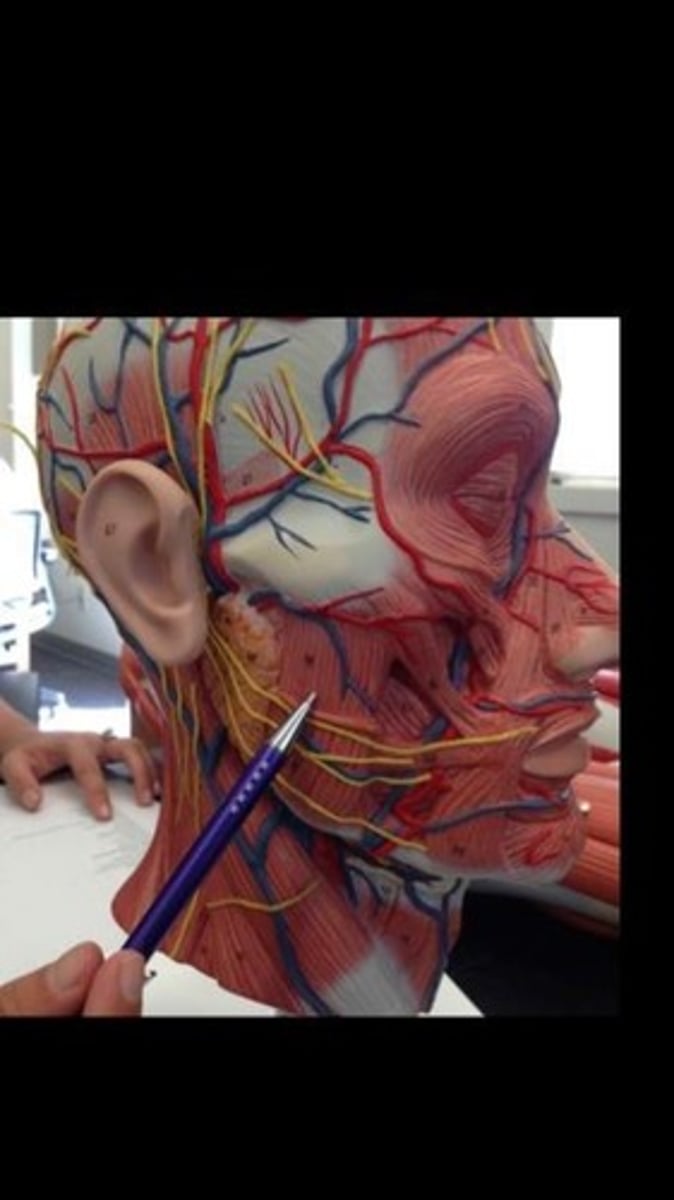

Occipitofrontalis

Orbicularis oris

Orbicularis oculi

Temporalis

Zygomaticus minor

Zygomaticus major

Buccinator

Masseter

Sternocleidomastoid